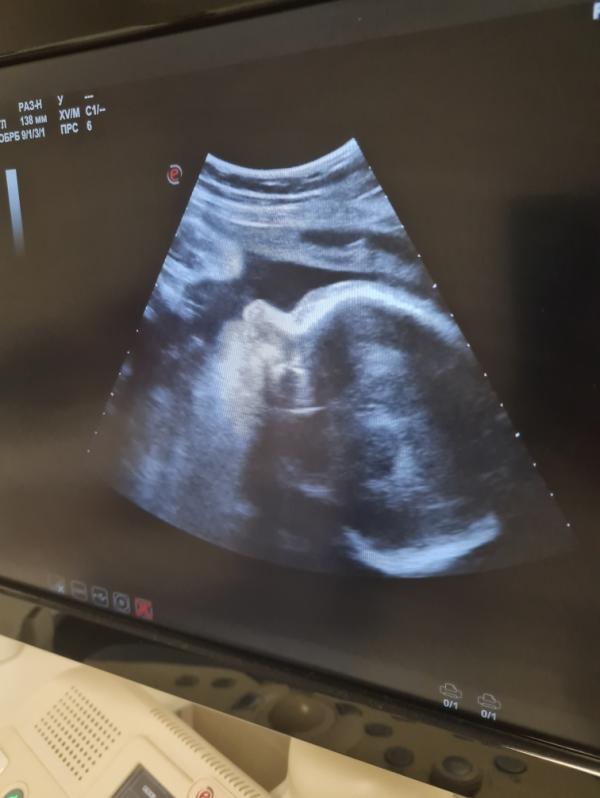

31 неделя беременности: УЗИ и КТГ - что увидели? Делимся результатами первого скрининга и впечатлениями

31 неделя наш профиль на узи👶 и первый ктг💪

1800 гр